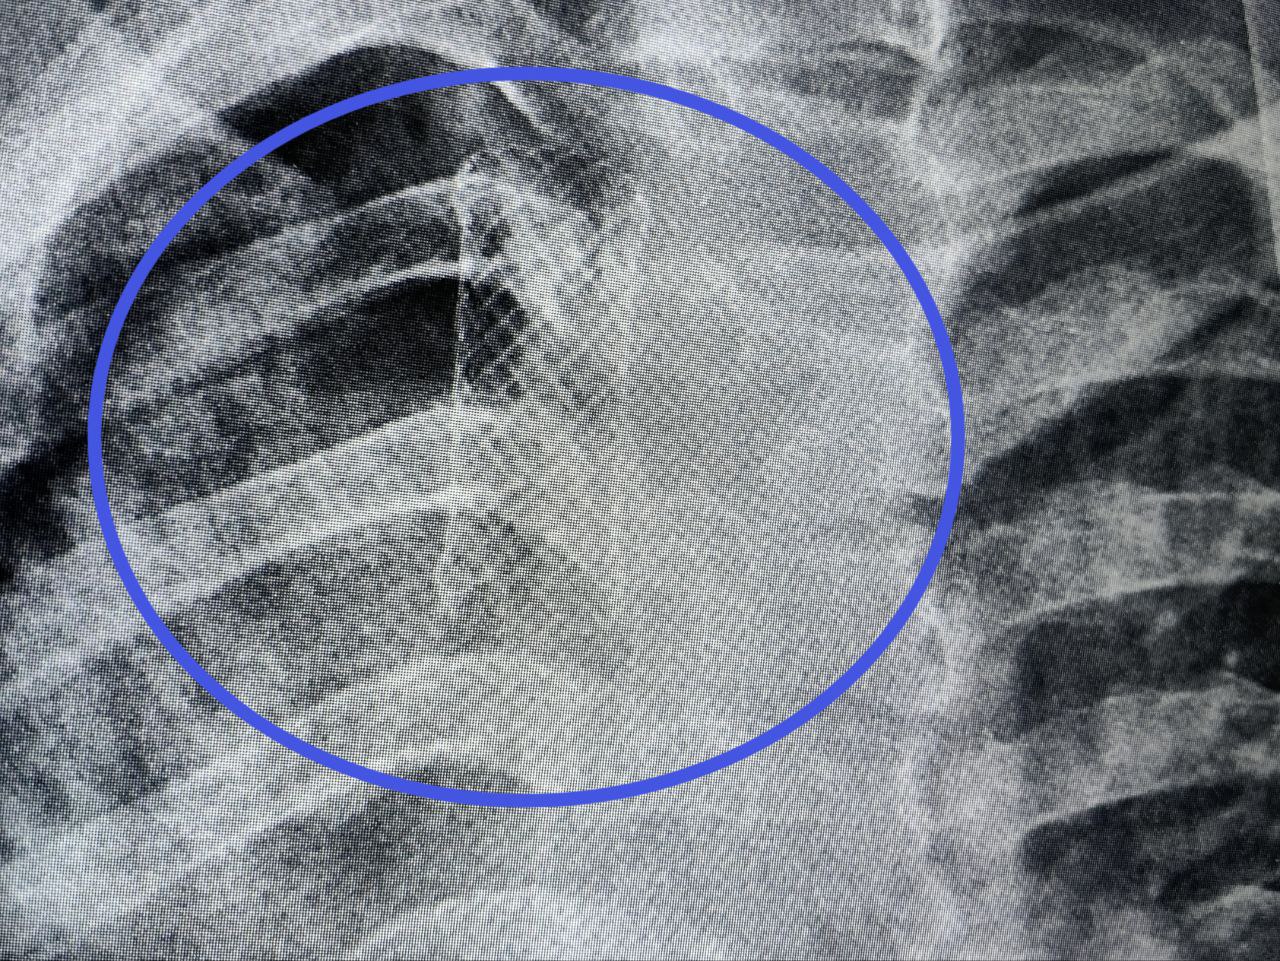

С редким отсроченным послеоперационным осложнением к нам поступил ребёнок. 15-летний пациент был доставлен с пневмотораксом. Из-за скопления воздуха в плевральной полости правое лёгкое настолько сжалось, что перестало участвовать в дыхательном процессе. Причину определили при бронхоскопии: дефект стенки трахеи. 5-миллиметровое отверстие стало местом сообщения с плевральной полостью, нарушив её герметичность, стерильность и вакуум. Воздух из трахеи заполнял пространство, где давление должно оставаться отрицательным, и стеснял лёгкое. Помимо трудностей с дыханием, ситуация может привести к развитию опасных гнойных воспалений плевры и средостения.